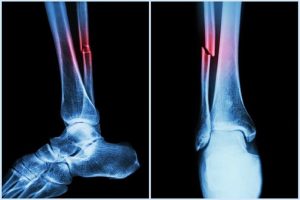

विशेषज्ञ: नई मशीन लर्निंग से दिल की बीमारी, फ्रैक्चर का पहले पता चलेगा!

इस सिस्टम की खासियत यह है कि यह रीढ़ की हड्डी की स्कैन इमेज (जिसे वीएफए कहा जाता है) देखकर पेट की मुख्य धमनी के कैल्सिफिकेशन (एएसी) की पहचान करता है। एएसी दिल के दौरे, स्ट्रोक और गिरने जैसे जोखिमों से जुड़ा होता है। ऑस्ट्रेलिया और कनाडा के वैज्ञानिकों ने एक नया एल्गोरिदम बनाया है, … Continue reading विशेषज्ञ: नई मशीन लर्निंग से दिल की बीमारी, फ्रैक्चर का पहले पता चलेगा!